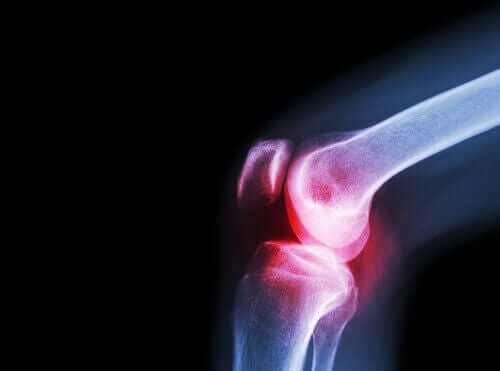

O outro sintoma prevalente do lúpus eritematoso sistêmico é a dor nas articulações. Ela é causada pela artrite desencadeada pela reação autoimune dentro do organismo. A evolução desta artrite se dá em crises agudas, com períodos sem dor e outros muito dolorosos.